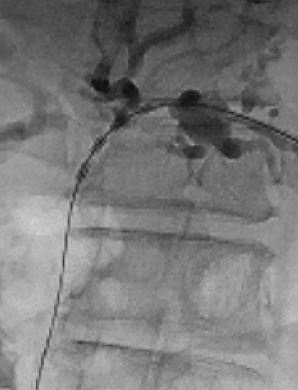

Fluoroscopic images demonstrate the use of ELRA™ in both the right and left hepatic ducts. These cases highlight the catheter’s ability to navigate complex ductal anatomies and deliver targeted ablation with precision. By restoring duct patency in strictures, ELRA™ provides a minimally invasive option that relieves obstruction and improves quality of life for patients.